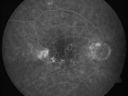

OD: Vertical C/D ratio is 0.1. There are hyperpigmented spots in the macula. There is no intraretinal or subretinal fluid.

Photos confirm clinical findings.

FLUORESCEIN ANGIOGRAM: Shows an occult subfoveal choroidal neovascular membrane in the left eye about 4 disc areas in size. The right eye has staining of drusen and hypofluorescence corresponding to the macular pigment. Temporal to the fovea, about 1-disc diameter from the center, there is a disc area of irregular hyperfluorescence. It is associated with a spot of hemorrhage, which may represent an occult asymptomatic extrafoveal choroidal neovascular membrane.